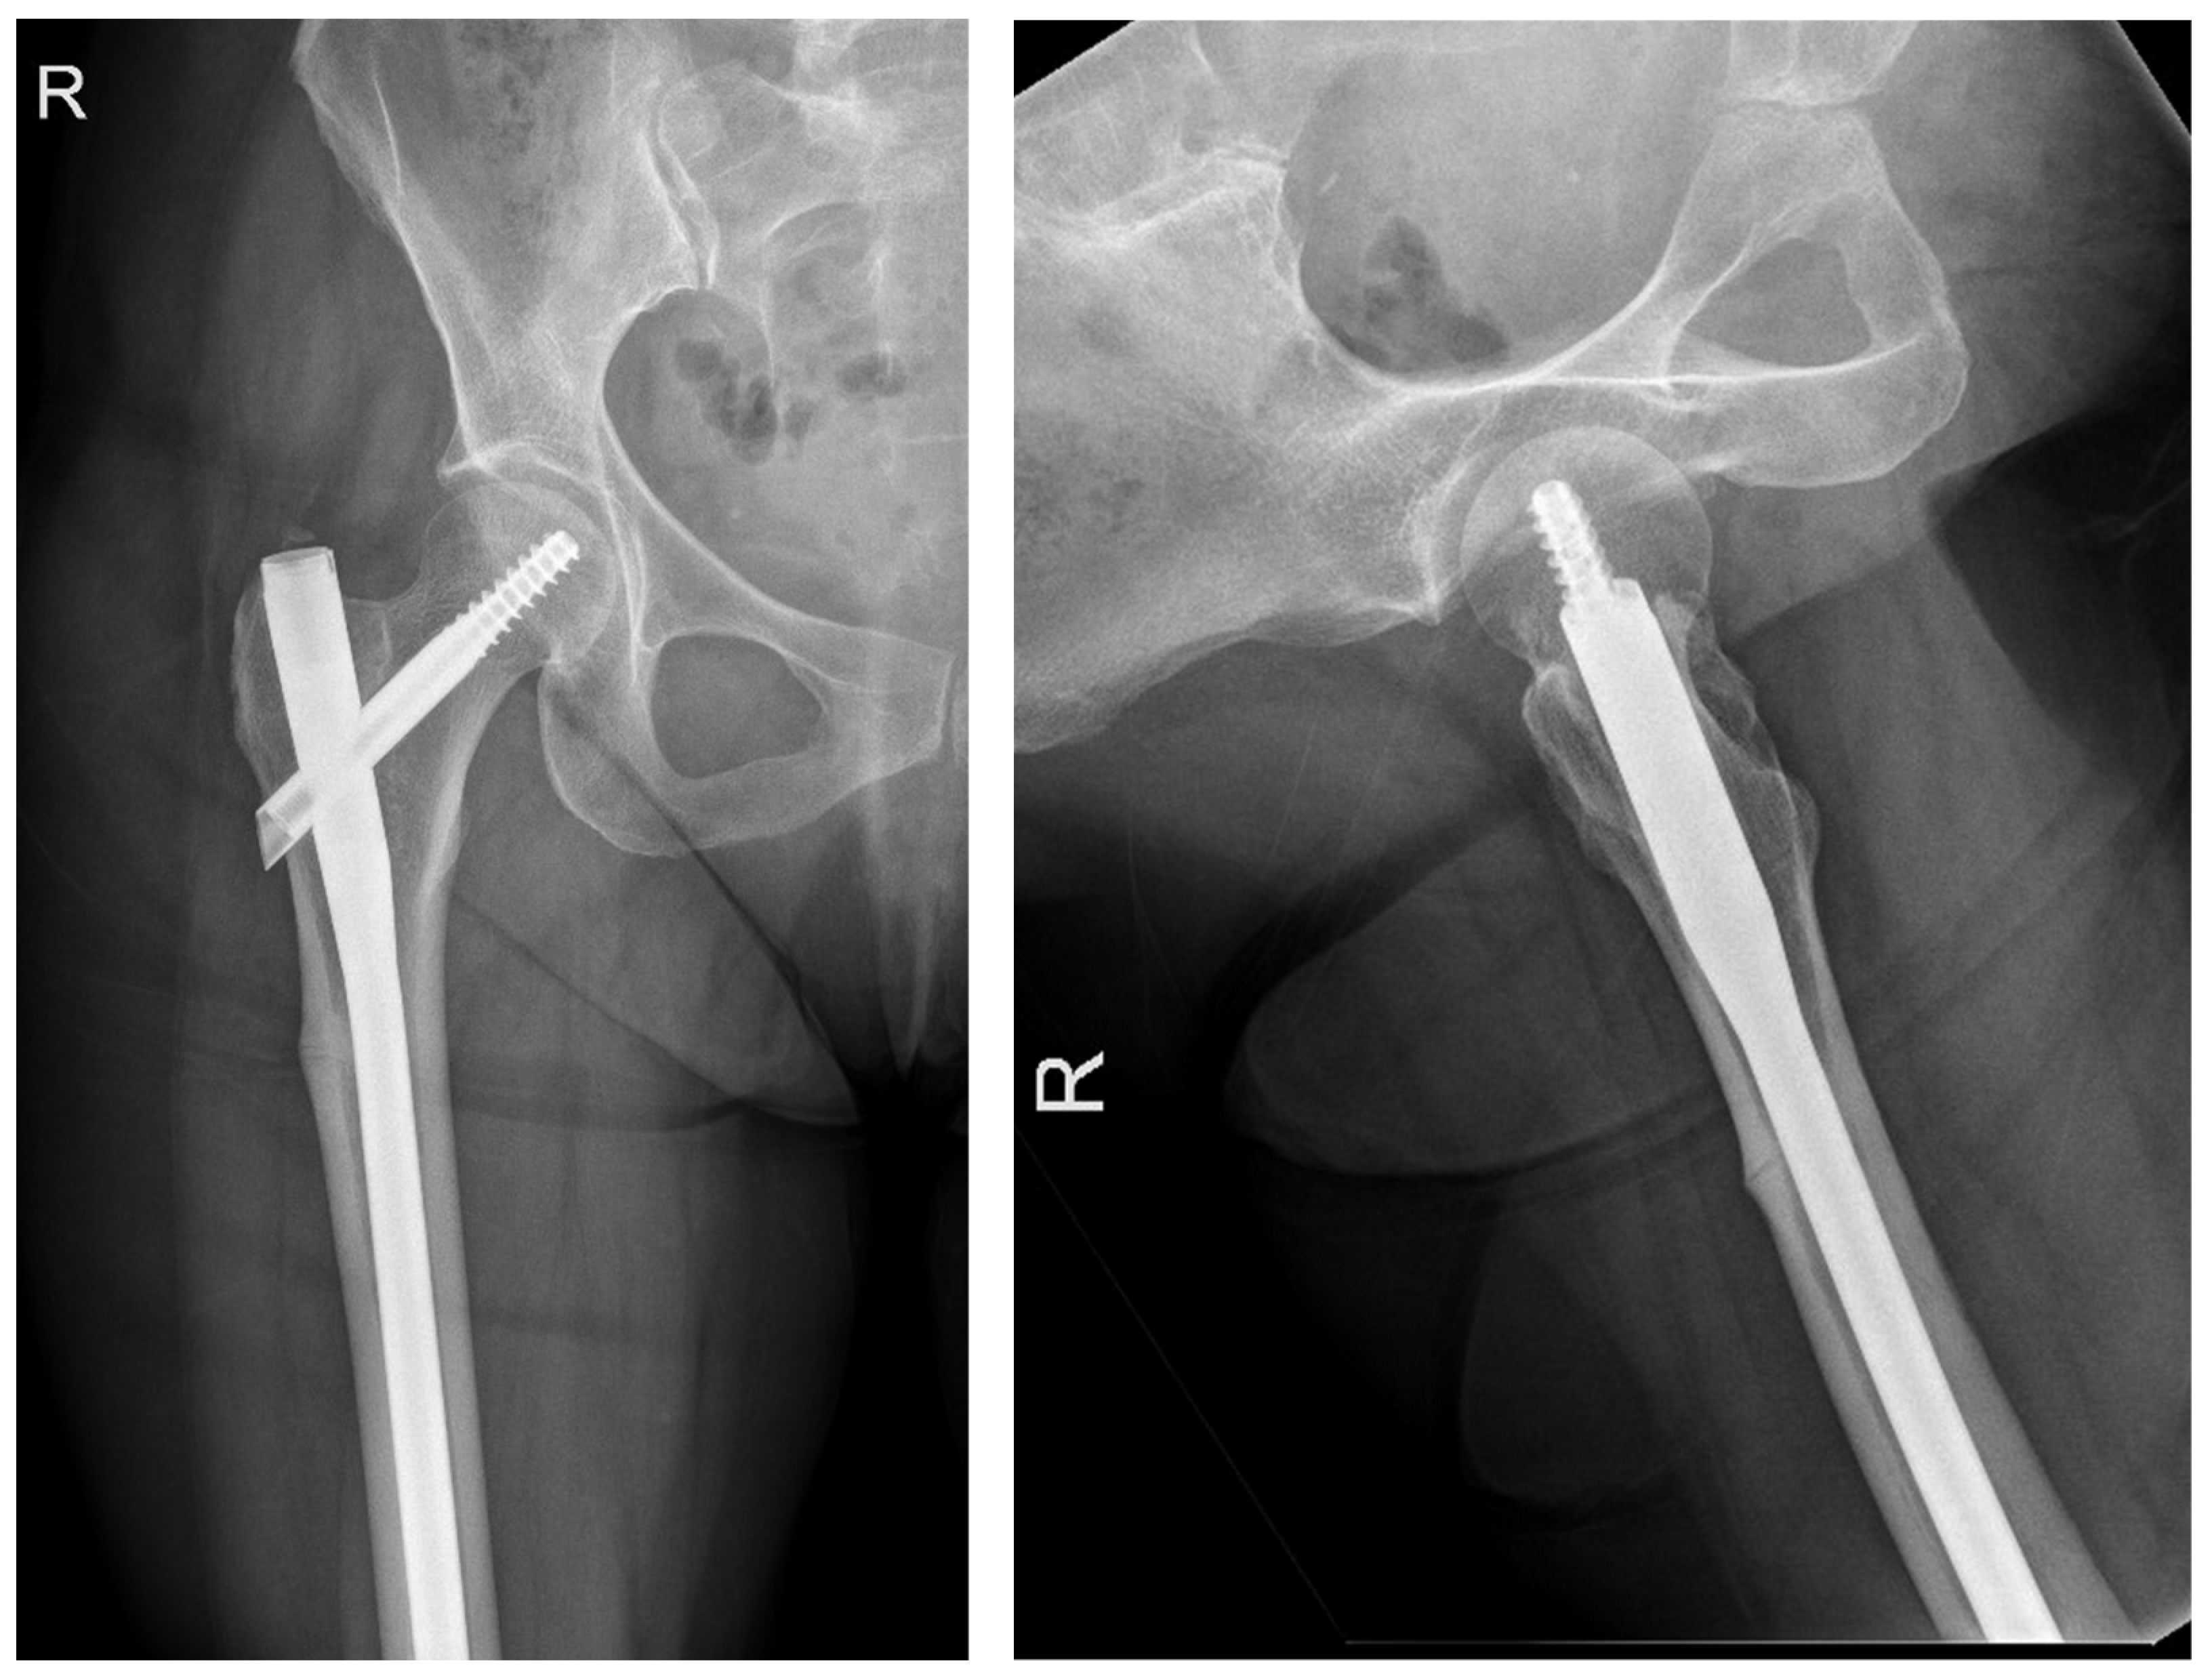

The following radiographs present the initial radiographs from the day of injury along with those obtained during the final OPD follow-up of the patient. The sequence presents radiographs demonstrating full radiological union (Scheme 1 and Scheme 2) and X-rays with no evidence of fracture healing at the final OPD follow-up (Scheme 3 and Scheme 4).

Scheme 1. X-ray of right hip AP view (left) and lateral view of right proximal femur (right) of atypical subtrochanteric fracture—September 2023.

Jcm 14 02858 sch001

Scheme 2. X-ray of right femur AP view (left) and lateral view of right hip (right) of atypical subtrochanteric fracture—September 2024 (radiological union).

Jcm 14 02858 sch002